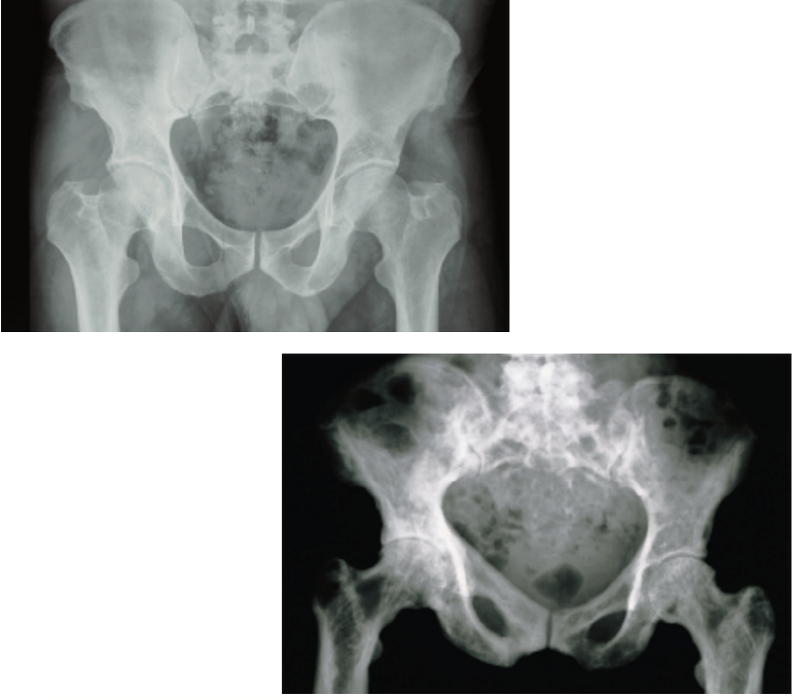

Osteitis Deformans

Haphazard bone deposit and resorption

Abnormally high ratio of spongy bone

Commonly affects the: spine, pelvis, femur, skull

3% of elderly North Americans – rare before 40